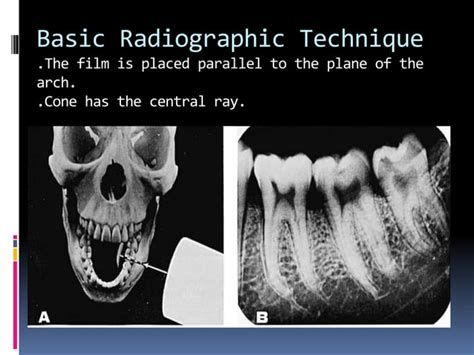

638×479

SlideShare

SLOB Technique